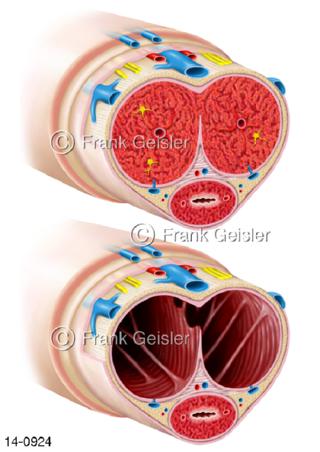

Bildergalerie Urogenitalsystem

Bilder zum Urogenitalsystem mit Urogenitalorgane, Urogenitaltrakt, zum Harn- und Geschlechtsapparat, Harnorgane und Geschlechtsorgane, Organe der Harnwege und der Fortpflanzung, Harnorgane und Geschlechtsorgane im männlichen und weiblichen Urogenitalsystem